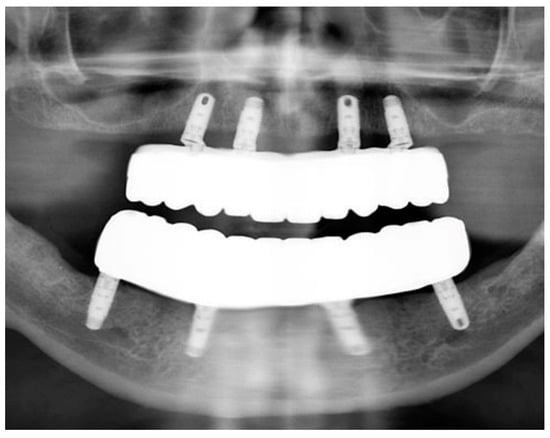

Full-Mouth Rehabilitation of a Patient with Sjogren’s Syndrome with Maxillary Titanium-Zirconia and Mandibular Monolithic Zirconia Implant Prostheses Fabricated with CAD/CAM Technology: A Clinical Report

2. Materials and Methods

3. Results